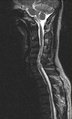

Within the spine, they most often occur in its thoracic part, although spinal chondrosarcomas represent only 7% of all these tumors. As in the case of osteosarcoma, they most often occur in the long bones. The therapy is primarily surgical, but chemotherapy or radiotherapy may be applied depending on the type and behavior of the tumor. [24][25][26]náhled|MRI – metastáza prsního karcinomu

Secondary extradural tumors[edit | edit source]

Secondary tumors of the spinal cord are caused by metastases of cancers from various areas of the body. The most common cancers are lung, breast, prostate, kidney, thyroid [2][3]. Extradural metastases represent about all 95% of spinal metastases [27].

The most frequently affected area of extraspinal metastases is the thoracic and lumbar segment of the spine - the cervical area is minimally affected [2].